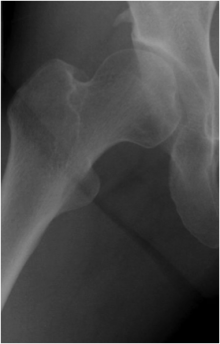

大腿骨骨切り術

寛骨臼回転骨切り術ができないような関節の状態で、年齢が若く、人工関節に抵抗を感じている場合には、大腿骨の骨きり術が可能な場合があります。特に外反骨きり術は30~40歳代の、末期股関節症に行うことがあります。(しかし、人工関節に比べて、術後のリハビリの期間が長く、症状や関節の動きの改善が十分でない場合もあり、人工関節が選択されることが多くなっています)。